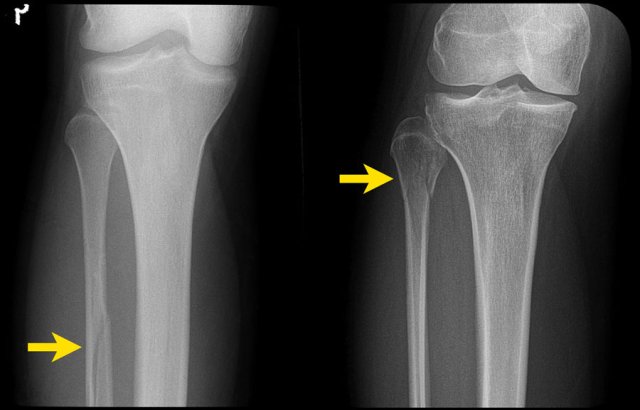

The left image is another example of an unstable bimalleolar fracture stage 2 Weber A.

The right image shows a vertical fracture of the medial malleolus (arrow). This is always stage 2 and unstable. It means that there already is stage 1, because the trauma mechanism always follows this strict order, first stage 1 and then stage 2.

The ring of stability is broken in two places (scroll).